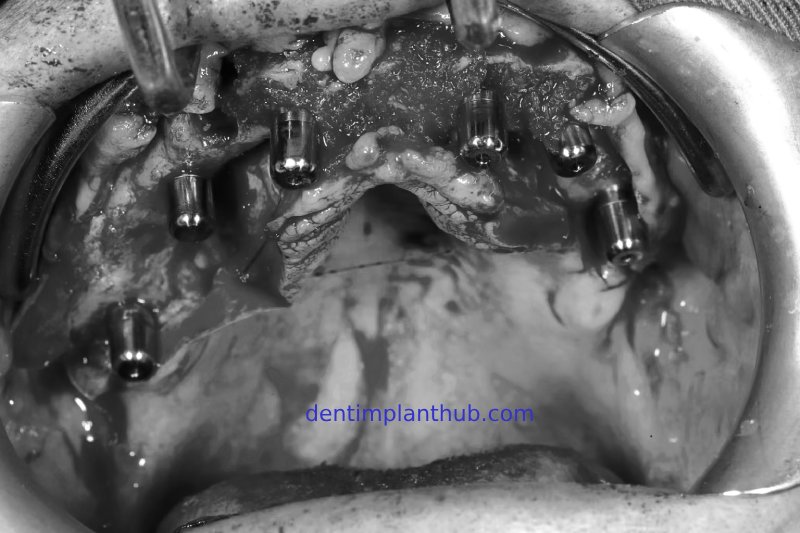

Photos taken during the implant surgery

The surgery was conducted on Wednesday, August 3rd, 2022, at 8:30 a.m. - For tooth 12, the implant model is 3612. - For tooth 14, the implant model is 4010, with 1 pack (0.25 grams) of bone powder and 1 piece of collagen sponge. - For tooth 18, the implant model is 4510, implanted at an inclination. - For tooth 22, the implant model is 3612. - For tooth 24, the implant model is 4010. - For tooth 26, the implant model is 5010, with internal maxillary sinus lift, and 1 pack (0.25 grams) of bone powder. - For tooth 45, the implant model is 4510. - For tooth 46, the implant model is 4510. - For tooth 36, the implant model is 4510, with immediate implant placement, and 1 pack (0.25 grams) of bone powder.